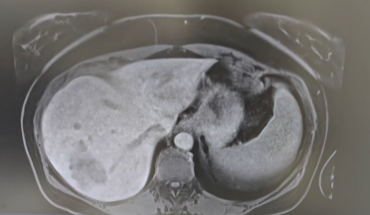

Liver

Pancreas